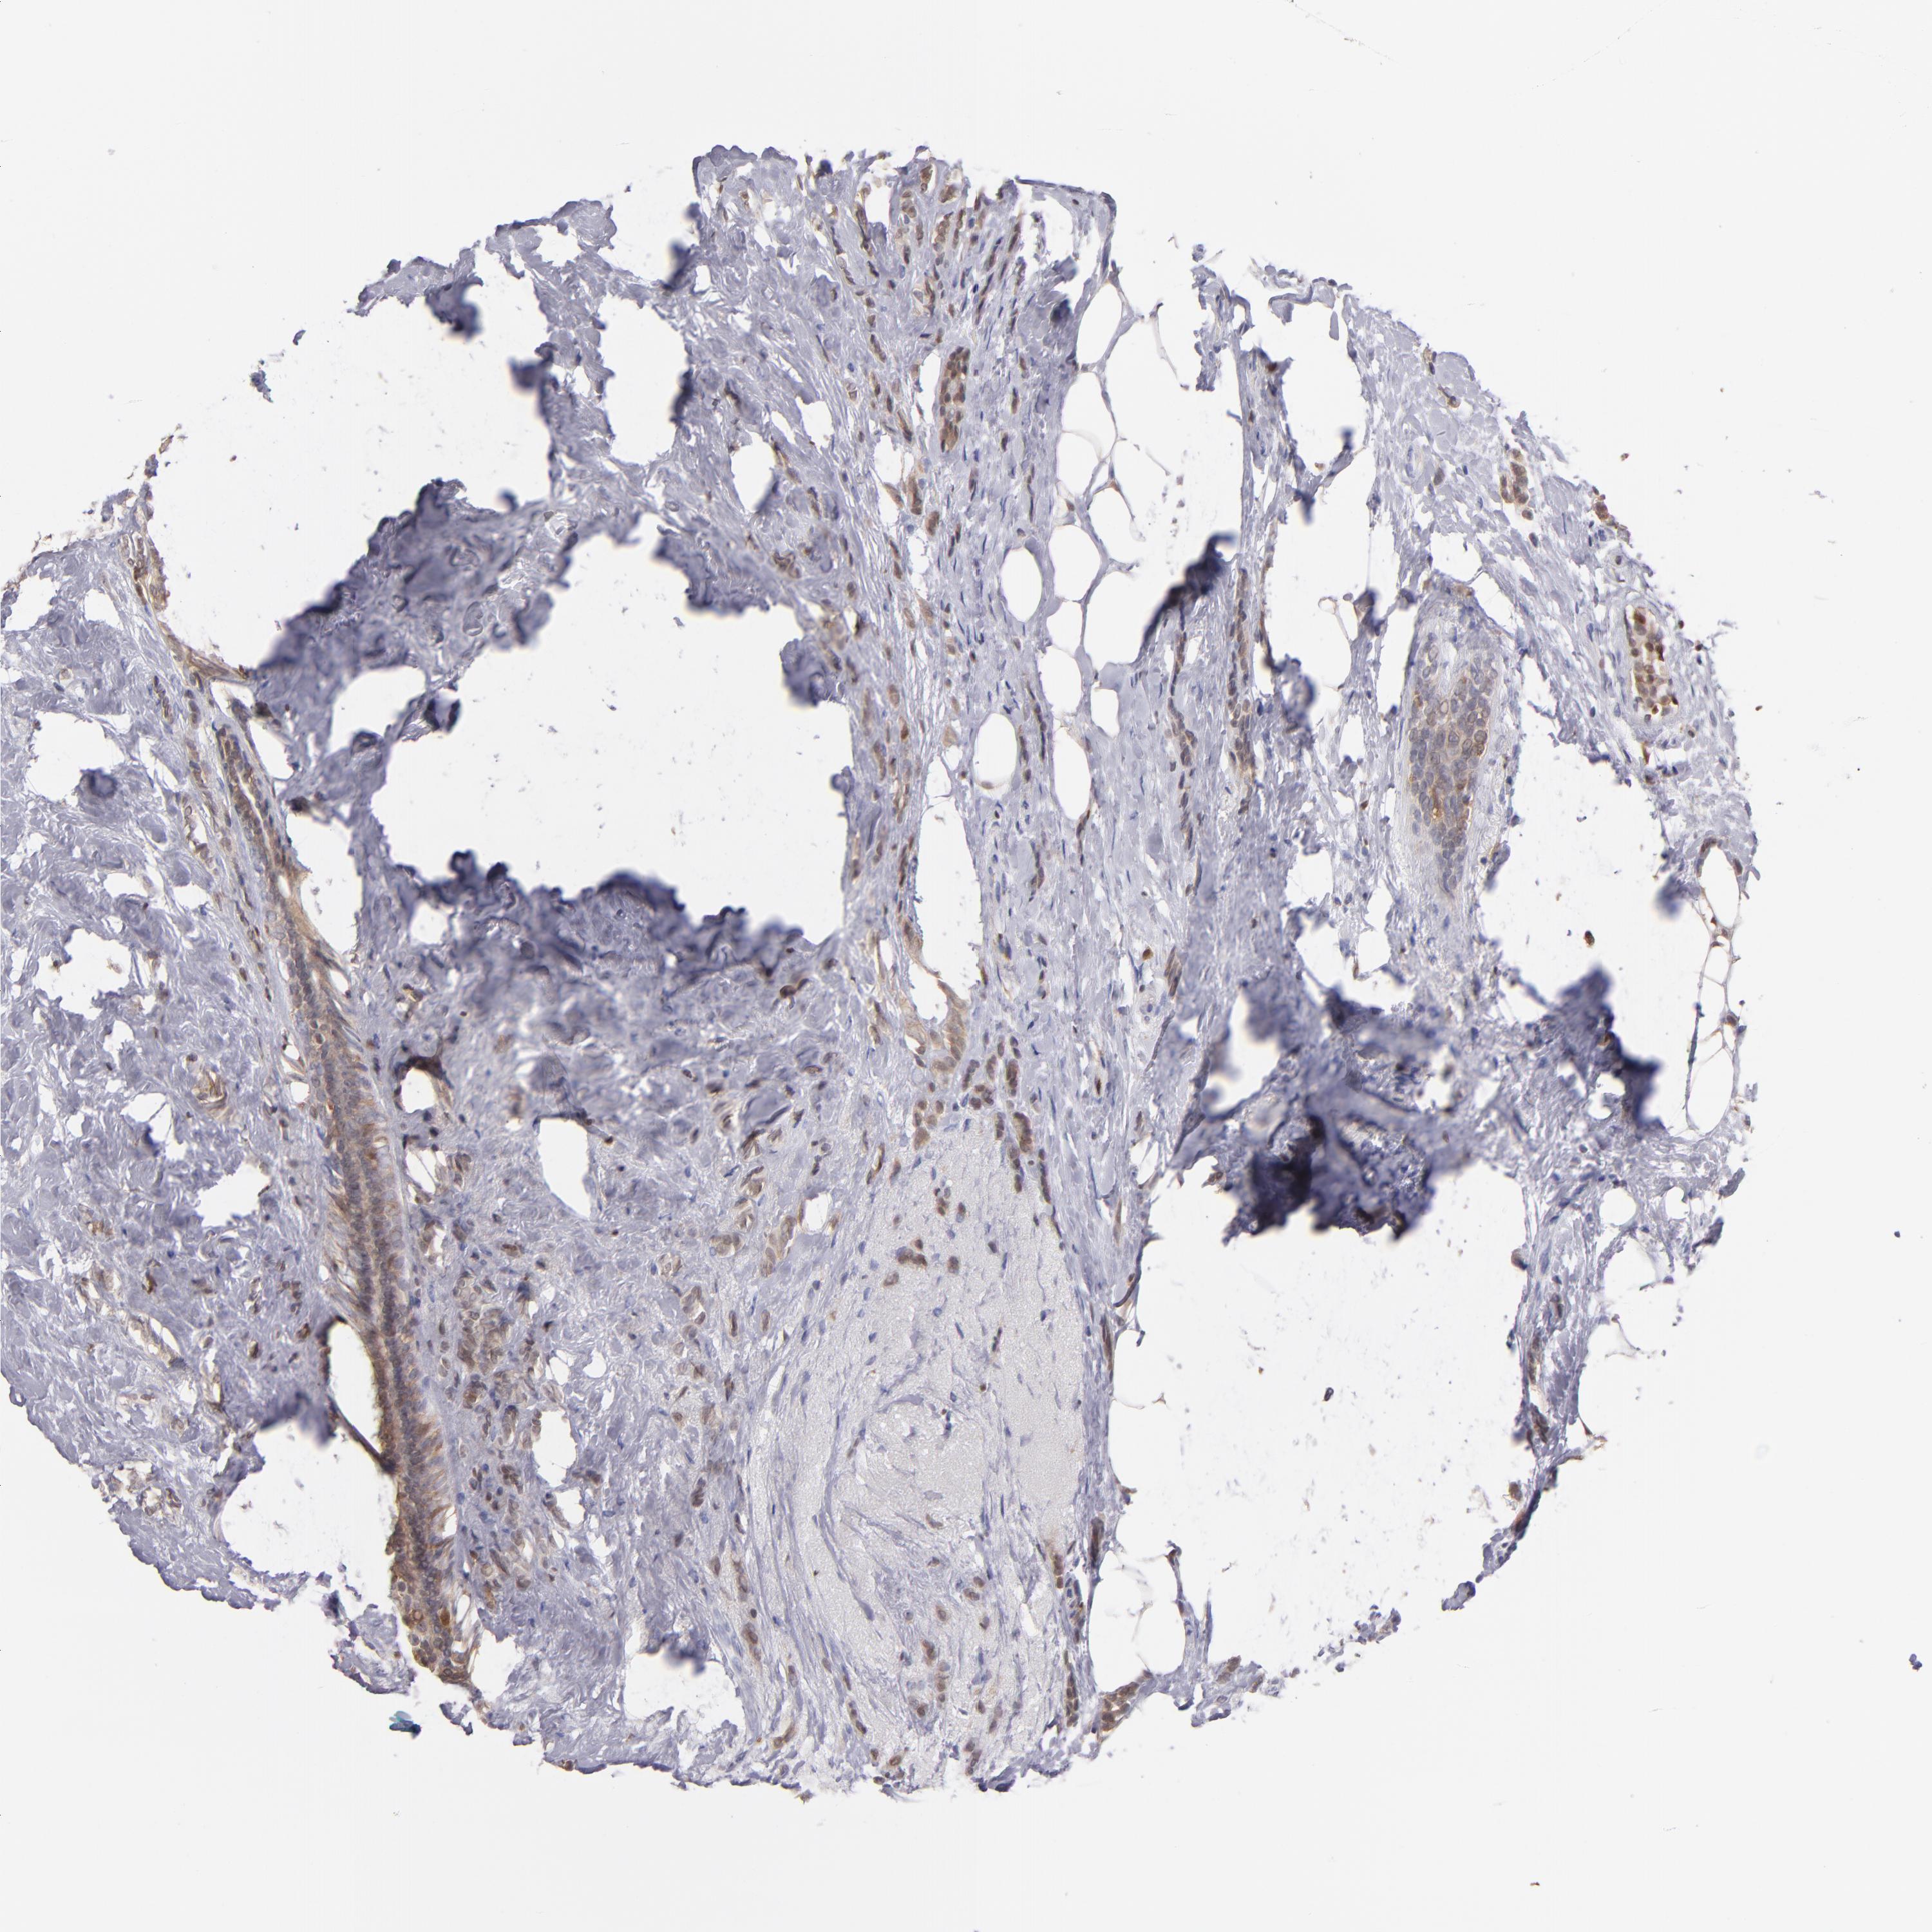

BRCA TCGA BRCA VALIDATION PROTEIN EXPRESSION